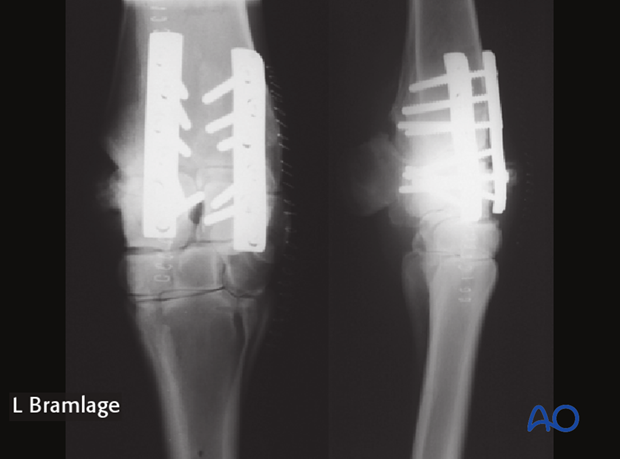

Radiographs are taken after all screws are inserted to assure that all screws are in the proper location and the joint is been well reduced.

After closure a sterile dressing is placed on the wound and a cast is applied from the elbow to the distal aspect of the metacarpus just above the metacarpophalangeal joint. Allowing the metacarpophalangeal joint to maintain flexion and extension greatly increases the ability of the horse to move comfortably postoperatively.

The cast is maintained in place for 30 days with a cast change at 2 weeks postoperatively. The cast change can be performed standing or under general anesthesia depending on patient compliance.

Follow up radiographs at 60 days will determine the next step in the reconvalescent period. Normally 30 days of gradually increasing exercise is recommended prior to resumption of free-choice exercise. Partial arthrodesis is for non-athletic purposes only.